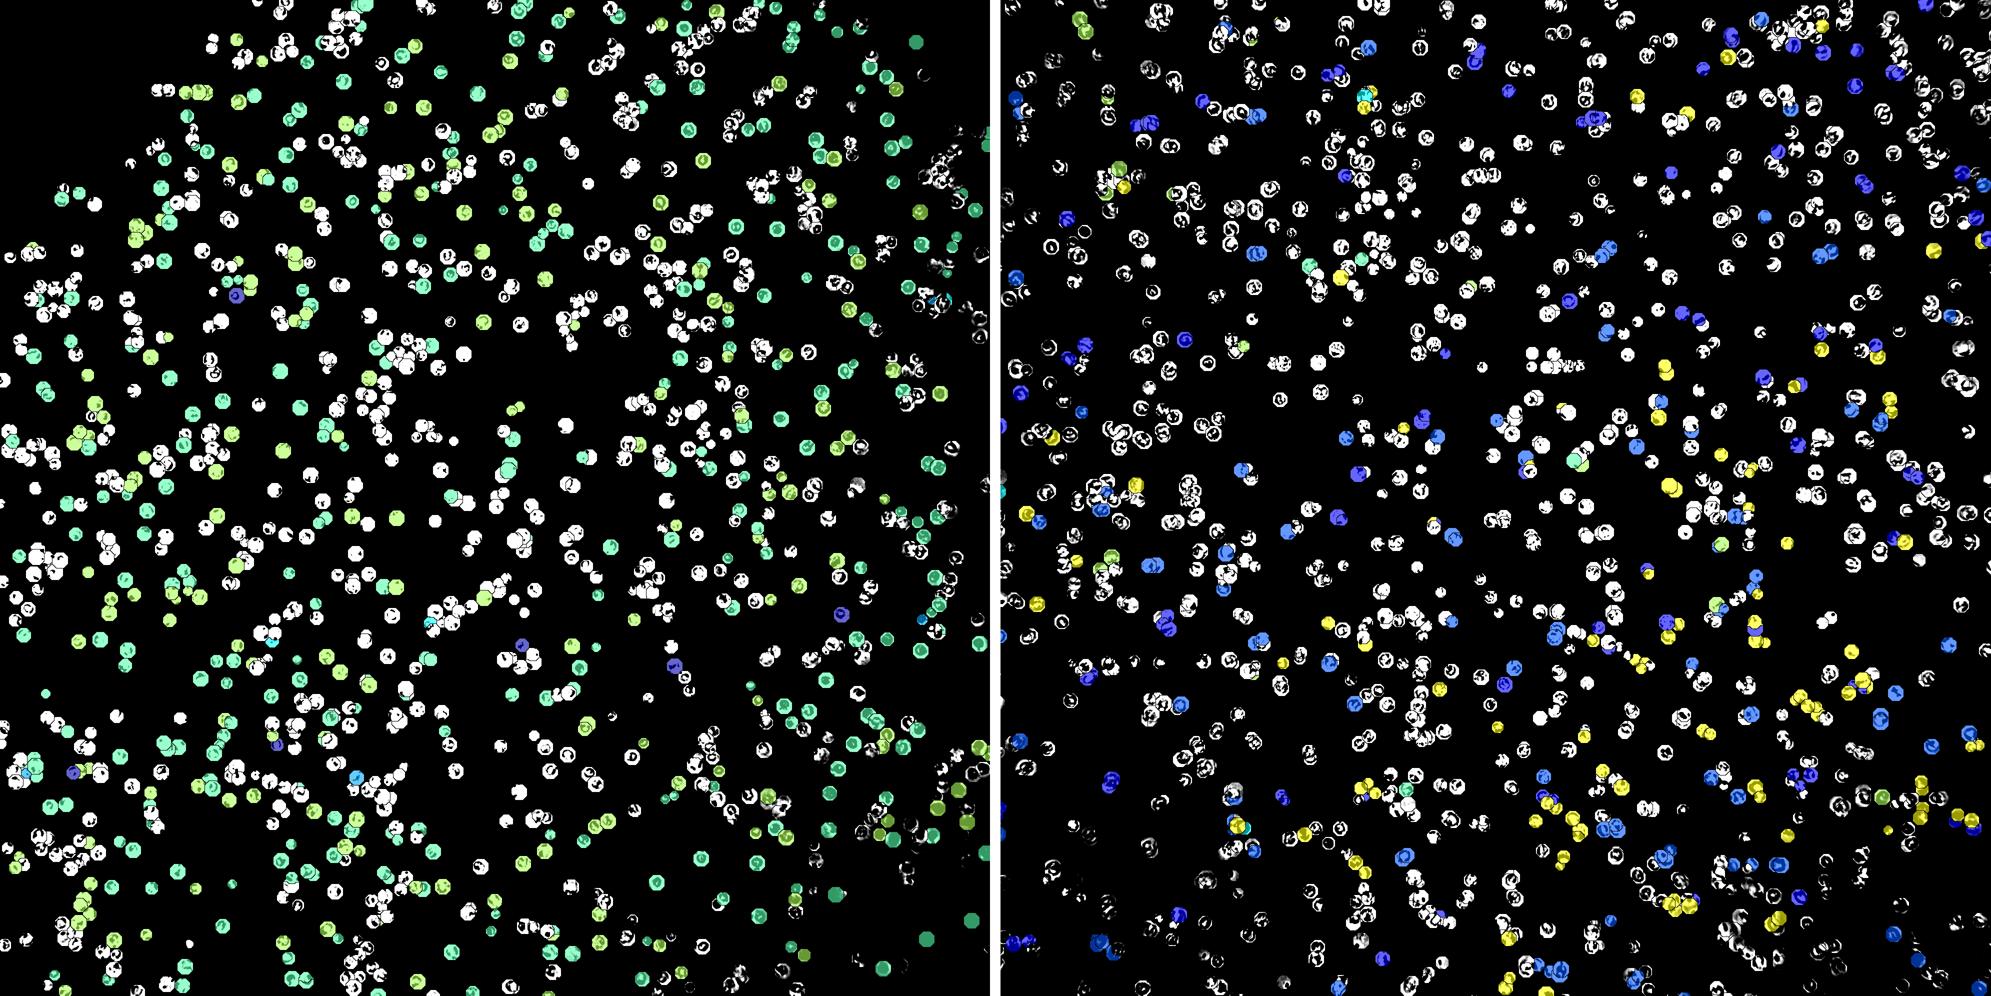

Cells labelled with CD8a TIA1

Peripheral blood lymphocytes

Inflammatory Disease

Cell populations before and after treatment